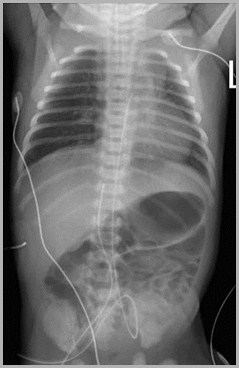

Two UACs, one at T7, the other at L3UVC in portal vein

T7

L3